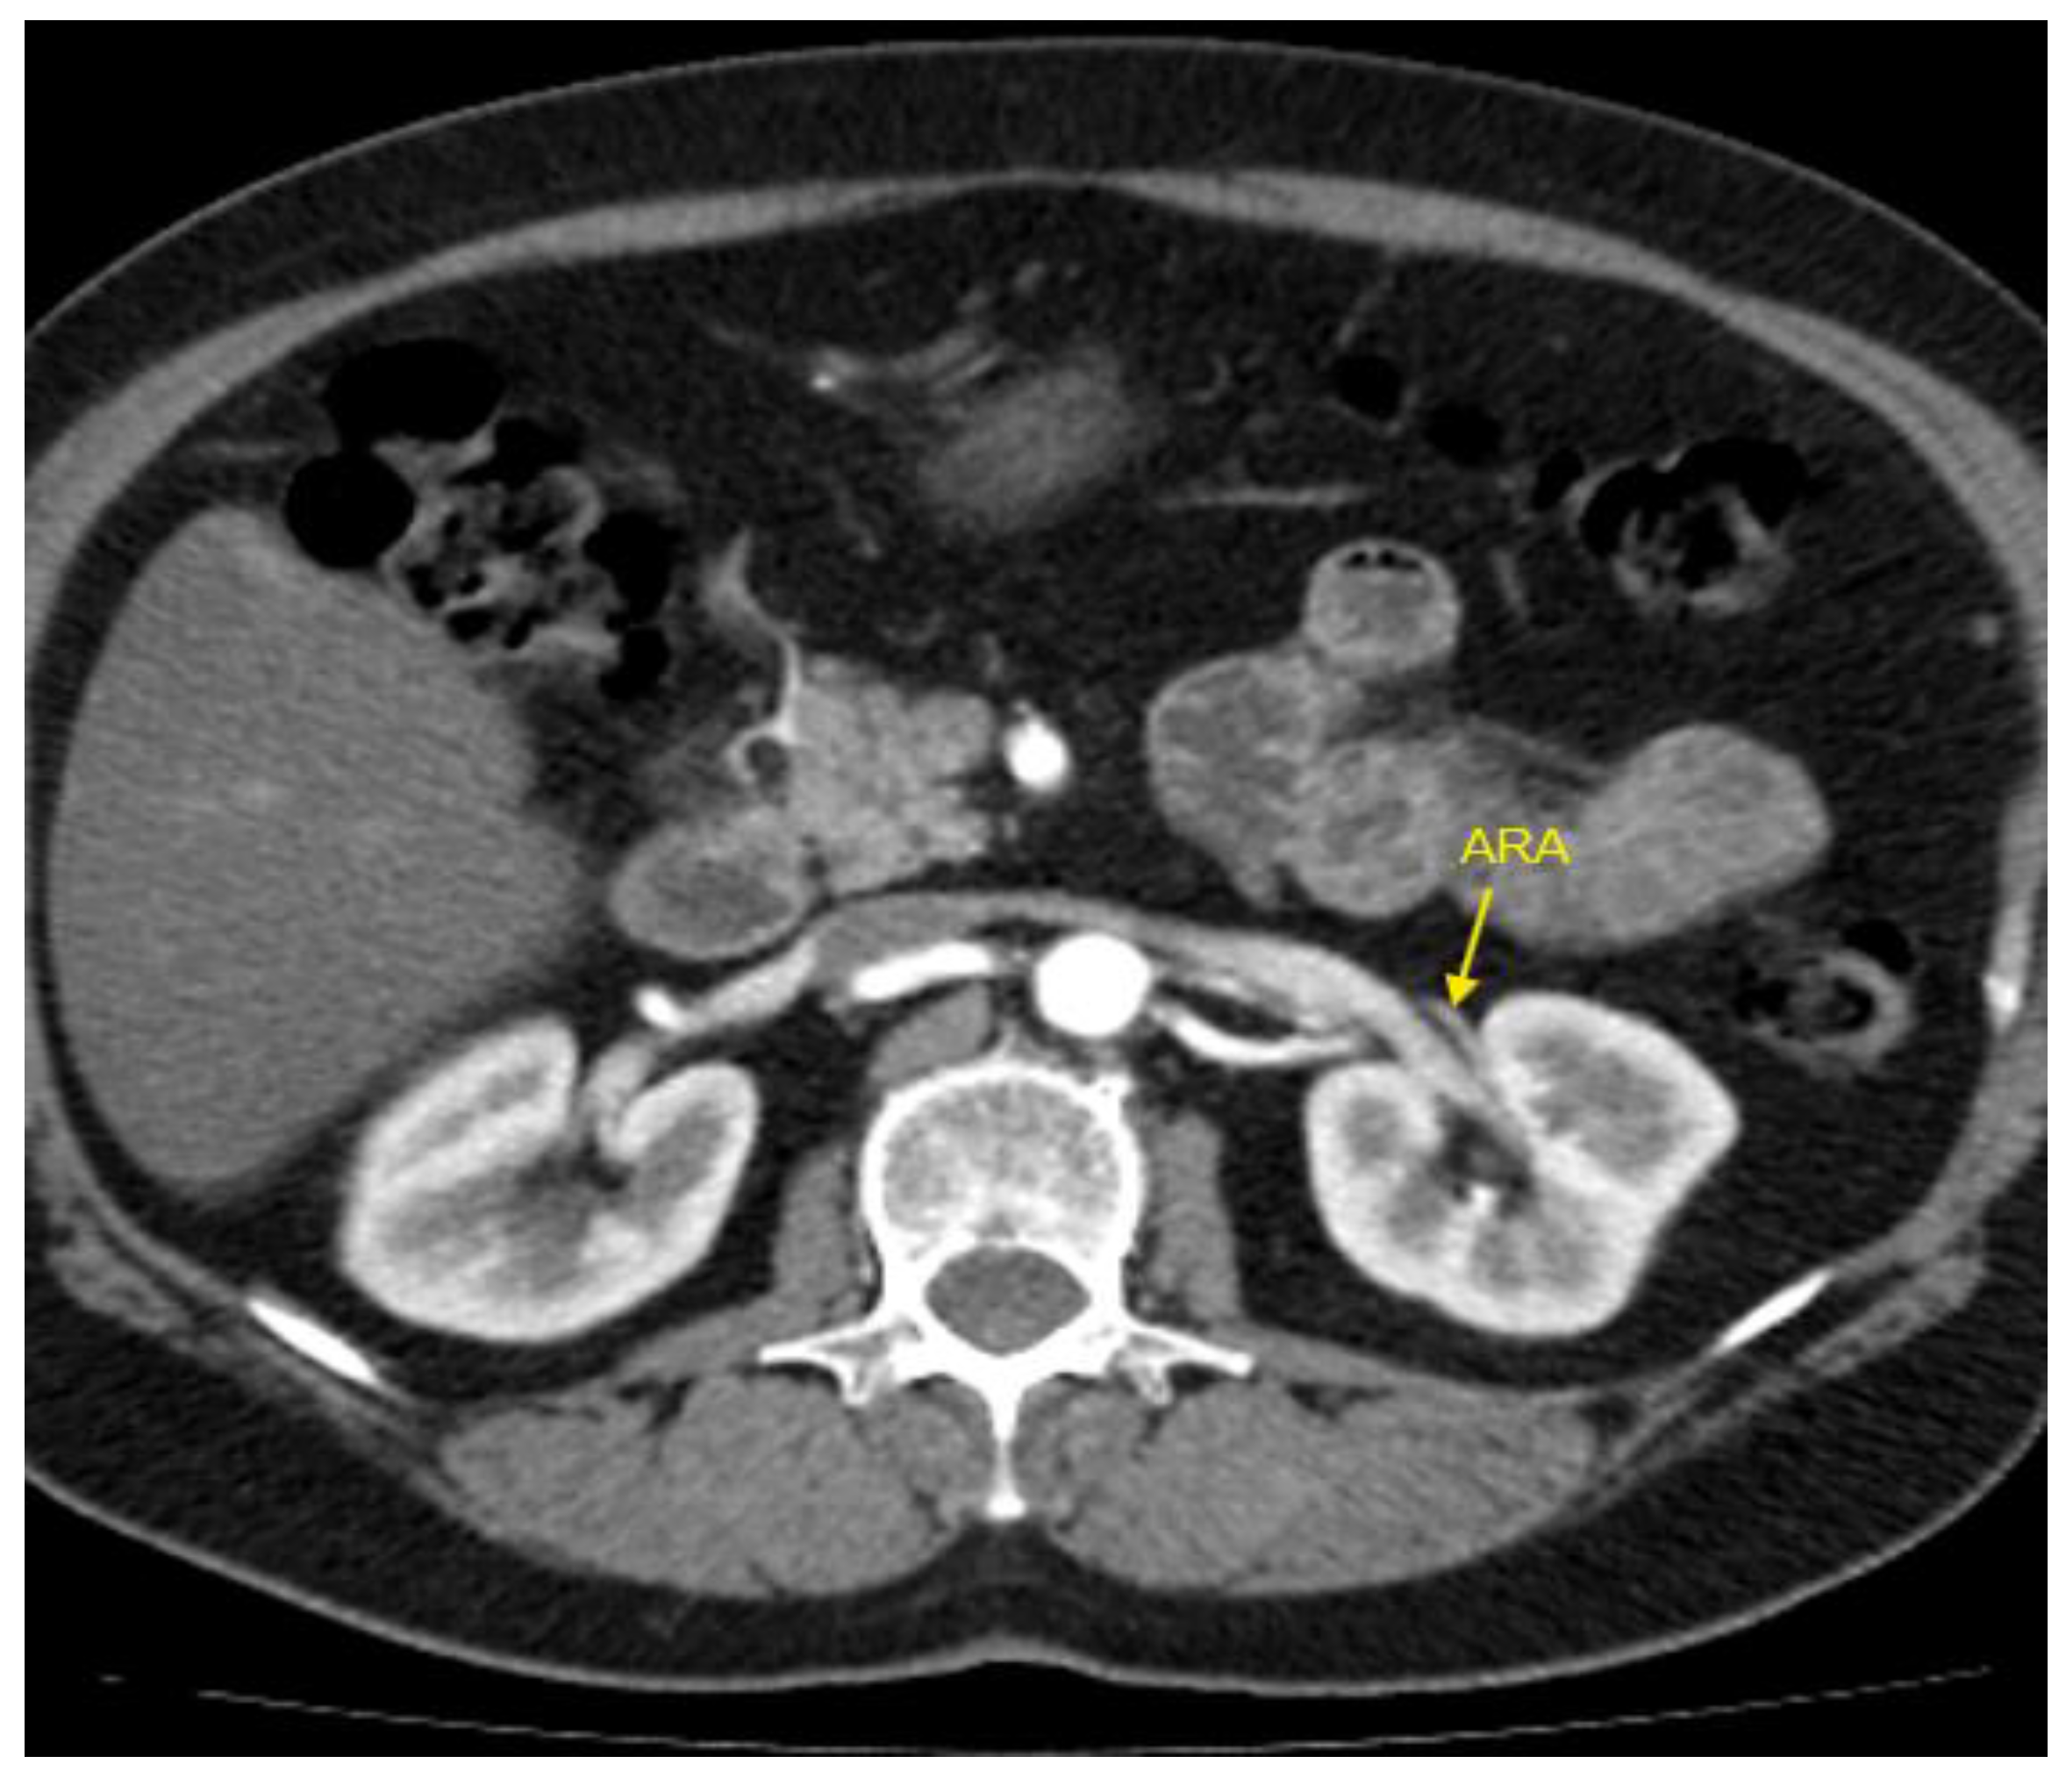

Figure 2. Contrast-enhanced CT imaging of a 47-year-old female patient revealed an accessory renal artery in the left kidney, indicated by the yellow arrow. The patient was hospitalized for resistant HTN that persisted despite treatment with a combination of four drugs. Her regimen included an angiotensin II receptor antagonist (valsartan), a dihydropyridine calcium channel blocker (slow-release nifedipine), a beta-blocker (bisoprolol), and a thiazide diuretic (hydrochlorothiazide), all administered at standard doses. ARA – accessory renal artery; CT – computed tomography; HTN – arterial hypertension.